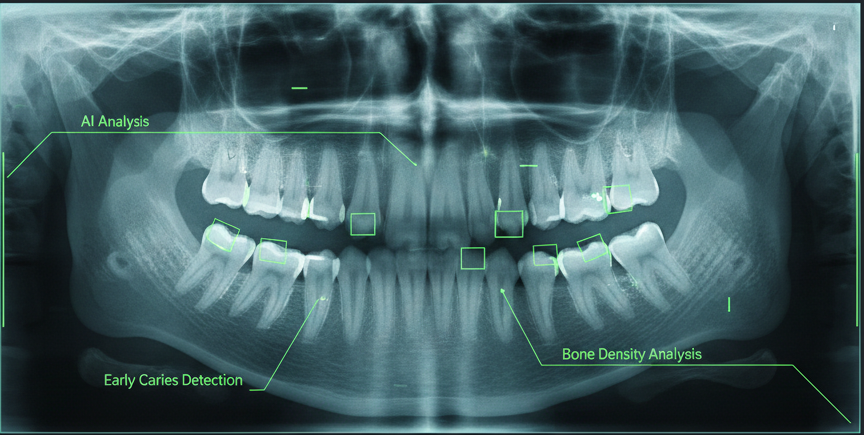

Um auch verborgene Strukturen sicher beurteilen zu können, setzen wir auf KI-unterstütztes Röntgen, das durch intelligente Algorithmen selbst feinste Kariesherde oder Knochenveränderungen frühzeitig erkennt.

Diese Kombination aus menschlicher Expertise und digitaler Intelligenz garantiert Ihnen eine Diagnose auf höchstem technischem Niveau. Durch dieses lückenlose Bild Ihrer Zahngesundheit können wir Behandlungen so schonend, sicher und planbar wie nie zuvor gestalten.